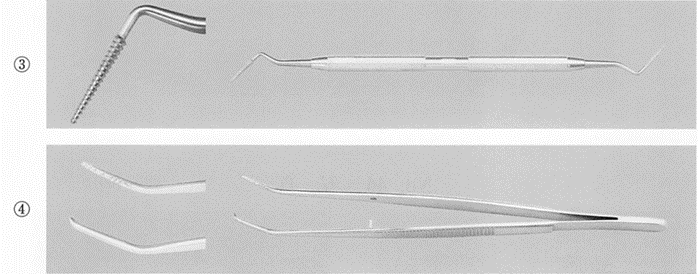

午前-95

30歳の男性。上顎右側第二小臼歯の一過性の冷水痛を主訴として来院した。検査の結果、コンポジットレジン修復を行うことになった。う蝕除去後の口腔内写真と器具の写真を別に示す。 次に使用するのはどれか。2つ選べ。

a. ①

b. ②

c. ③

d. ④

解答を見る

a.c